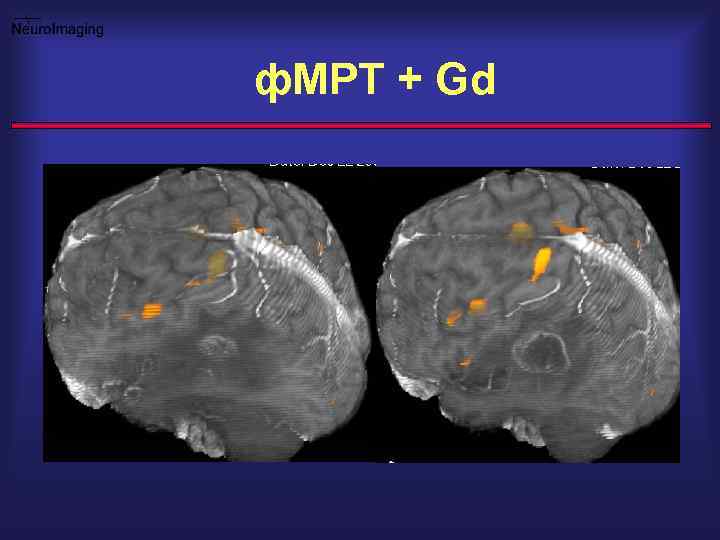

ф. МРТ + Gd

Опухоль парацентральной зоны Опер. подход ? -двигат. центр руки ? -КСП тракт ? -Анатомические ориентиры ?